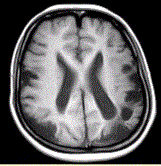

问题 女性,22岁。癫痫发作及智力异常。MRI显示见下图。 为进一步明确诊断,下一步的影像学检查首选

选项 A.MRI增强 B.FLAIR C.DWI D.MRA E.MRV F.DSA

答案 D

解析 D